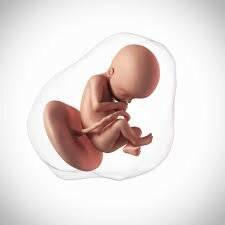

• weeks 28-29

weeks 28-29

Development of baby weeks 28-29

• Period: to

The baby's eyes begin to partially open. The central nervous system directs breathing and body temperature and the lungs can breathe. The baby now kicks and stretches and is at 10 inches and 2 1/4 pounds.